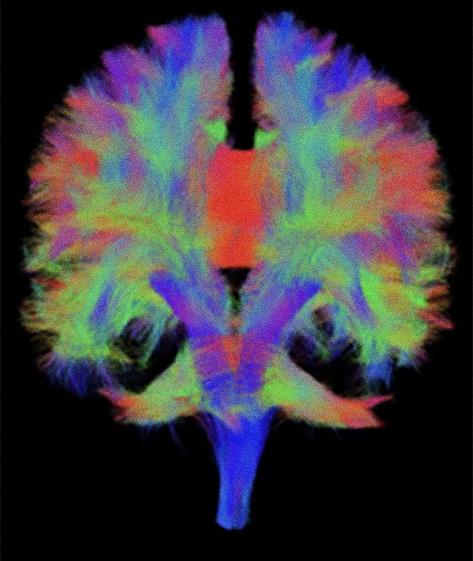

Des études récentes en électroencéphalographie (EEG) ont montré que lorsque les jeunes adultes se concentrent sur des informations auditives pertinentes, l’activité cérébrale rythmique alpha (ondes cérébrales de fréquence 9-12Hz) augmente dans le cortex visuel.

L’activité cérébrale alpha peut être utilisée comme biomarqueur des mécanismes de l’inhibition (capacité de blocage), qui désactive les zones cérébrales sensorielles peu utilisées lors d’une tâche. En d’autres termes, l’alpha dans les aires visuelles indique que la vision est peu sollicitée et permet de prioriser l’activité dans les zones auditives : ceci permet de se concentrer sur l’écoute au détriment de la vision.

Les adultes plus âgés ont, sur le plan du comportement, plus de difficultés à se concentrer sur ce qu’ils écoutent, si on les compare à leurs pairs plus jeunes. Les aînés montrent moins d’alpha dans les régions cérébrales visuelles lorsqu’ils se concentrent sur des informations auditives. Ceci indique que leurs mécanismes d’inhibition sont moins efficaces que ceux des sujets plus jeunes : ils ont plus de difficultés à bloquer les informations distrayantes lors de tâches d’écoute.

L’objectif de notre projet de recherche est d’utiliser la SMTr

pour venir induire, artificiellement, une activité alpha dans les zones visuelles du cerveau d’aînés alors même qu’ils réalisent une tâche d’écoute attentive. Notre hypothèse est qu’il est possible d’aider le cerveau des aînés à bloquer le traitement des informations distrayantes et, par là même, de pousser l’attention à rajeunir.

Par ailleurs, les images d’IRM de type T1 (figure 6, à gauche) permettront aux chercheurs d’inférer exactement d’où viennent les modifications de l’activité cérébrale entraînées par la SMTr chez les participants au protocole de recherche. Grâce à certaines techniques d’analyse (méthode de reconstruction de sources), il est possible de déterminer de quelle zone du cerveau provient le signal électrique enregistré grâce à l’EEG. Lorsque les images anatomiques sont disponibles pour chaque participant, la précision des analyses augmente considérablement. En utilisant ce type d’analyse et en comparant des groupes d’individus jeunes et âgés, nous pourrons déterminer si notre protocole permet de rajeunir le fonctionnement cérébral, et, si oui, dans quelles zones précises du cerveau

ce phénomène est-il observable. Ce protocole de recherche prévoit également l’acquisition d’images de diffusion (figure 6, à droite). Ces images permettent d’étudier la structure des fibres de matière blanche, les tracts qui, dans le cerveau, relient les différentes zones de matière grise entre elles. Grâce à ce type d’images, les chercheurs pourront déterminer si les caractéristiques structurelles des faisceaux de matière blanche jouent un rôle dans la réponse à la neurostimulation chez les individus jeunes et chez les aînés. On peut par exemple imaginer que l’intégrité structurelle des faisceaux de matière blanche reliant les zones du cerveau impliquées dans l’attention (p. ex. : les faisceaux longitudinaux supérieurs I, II et III) sera positivement corrélée à l’effet bénéfique induit par le protocole de neurostimulation, et ce, indépendamment de l’âge des participants.